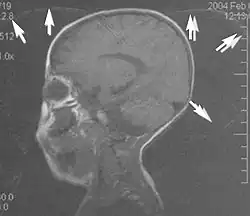

Metal artifacts

Metal artifacts occur at interfaces of tissues with different magnetic susceptibilities, which cause local magnetic fields to distort the external magnetic field. This distortion changes the precession frequency in the tissue leading to spatial mismapping of information. The degree of distortion depends on the type of metal (stainless steel having a greater distorting effect than titanium alloy), the type of interface (most striking effect at soft tissue-metal interfaces), pulse sequence and imaging parameters. Metal artifacts are caused by external ferromagnetics such as cobalt containing make-up, internal ferromagnetics such as surgical clips, spinal hardware and other orthopaedic devices, and in some cases, metallic objects swallowed by people with pica.[3] Manifestation of these artifacts is variable, including total signal loss, peripheral high signal and image distortion (Figs 3 and 4).[1] Reduction of these artifacts can be attempted by orientating the long axis of an implant or device parallel to the long axis of the external magnetic field, possible with mobile extremity imaging and an open magnet. Further methods used are choosing the appropriate frequency encoding direction, since metal artifacts are most pronounced in this direction, using smaller voxel sizes, fast imaging sequences, increased readout bandwidth and avoiding gradient-echo imaging when metal is present. A technique called MARS (metal artifact reduction sequence) applies an additional gradient, along the slice select gradient at the time the frequency encoding gradient is applied.